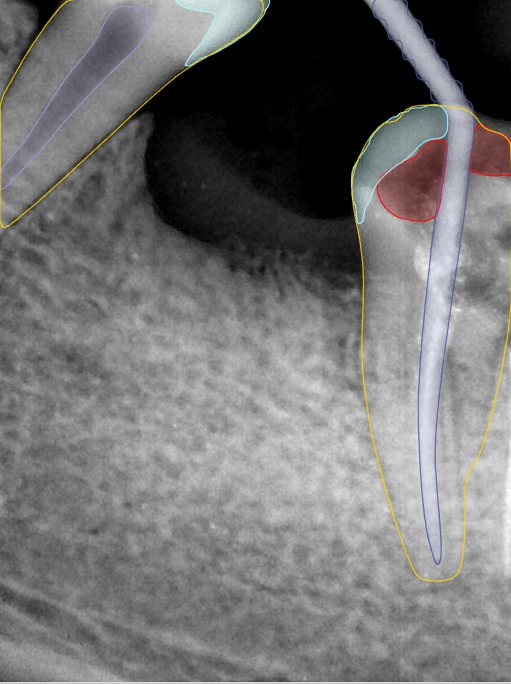

CR/DR 牙齿分割阶段记录

当前进展

- 完成了 CR/DR 牙齿相关分割训练

- 当前结果已经达到阶段预期,但仍有细节问题需要继续处理

相关测试

遇到的问题

- 训练过程中出现过 mask 下移问题

- 部分结果会出现 box 填充异常

- mask 边缘仍然有比较明显的锯齿感